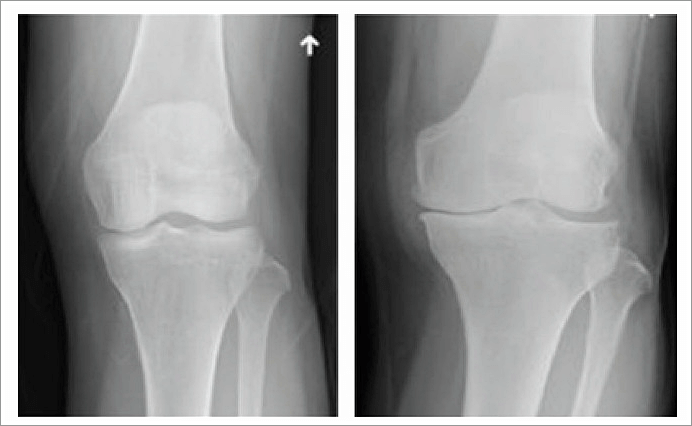

1. 골관절염 (퇴행성 관절염)

관절 연골이 닳아 없어지면서 국소적인 퇴행성 변화가 나타나는 질환이다. 반복적인 작업이나 운동 등 연골을 오랜 세월동안 무리하게 사용하는 것, 비만으로 관절에 무리를 많이 주는 것, 관절 외상 등이 원인이 될 수 있다.

정상적인 연골은 뼈 표면에 3~5mm정도로 푹신하고 미끌미끌한 형태를 유지하는데, 이 연골이 충격이나 과사용 등으로 벗겨지면, 관절이 스스로 보호하려는 염증 물질을 배출하면서 시리고 아픈 느낌이 생긴다 연골 중 무릎의 체중을 받쳐주는 반월상 연골이 손상되면 퇴행성관절염이 특히 잘 생긴다.